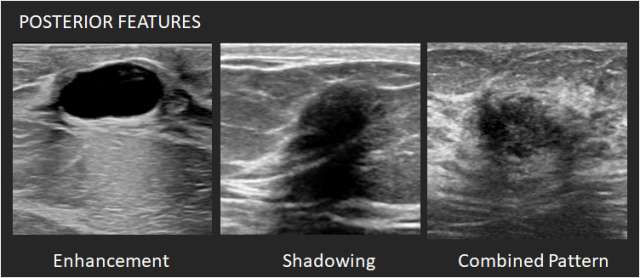

Posterior features: Posterior features represent the attenuation characteristics of a mass in respect to its acoustic transmission.

1. No posterior features – Neither posterior shadowing or enhancement is seen.

2. Enhancement – There is a column that is more echogenic deep to the mass. One criterion for cyst diagnosis is enhancement.

3. Shadowing – There is attenuation of acoustic transmission with the area posterior to the mass appearing darker. Shadowing is associated with fibrosis, with or without an underlying carcinoma. Macrocalcifications can also cause shadowing.

4. Combined pattern – There is more than one pattern of posterior attenuation.

Ultrasound Mass Posterior Features